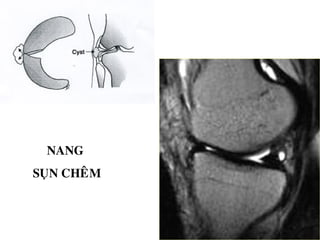

NANG

SUÏN CHEÂM